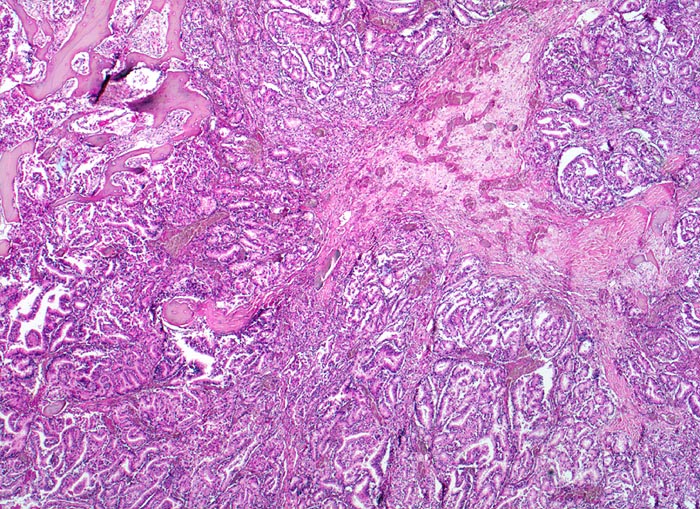

Staats/ Prostatakarzinom: Knochenmetastase

Prostatakarzinom: Knochenmetastase

Da Adenokarzinome neben der Prostata in fast allen Organen vorkommenen, ist die Differentialdiagnose im HE Schnitt bei Nachweis einer Knochenmetastase eines Adenokarzinoms sehr breit. Die immunhistochemische Positivität der Tumorzellen für prostataspezifisches Antigen (PSA) spricht für eine Primärtumorherkunft aus der Prostata. Prostatakarzinome bilden typischerweise osteoplastische Knochenmetastasen. Die Knochenbildung erfolgt via Cytokine und Wachstumsfaktoren, die von den Tumorzellen gebildet werden (z.B. TGF-beta), durch Stimulation der Osteoblasten, wahrscheinlich bei gleichzeitiger lokaler Reduktion der Osteoklastenaktivität (RANK/RANKL/OPG-System). Die Stimulation von Osteoblasten führt zu einer vermehrten appositionellen Osteoidneubildung entlang vorhandener Trabekel mit nachfolgender Mineralisierung. Durch fortgeschrittene Knochenneubildung kommt es zu einer vollständigen Ummauerung grösserer Tumorareale, welche durch die verminderte Blutzufuhr nekrotisch werden. Vielfach lassen sich histologisch osteoplastische und osteolytische Anteile nachweisen. Immunhistochemisch lässt sich in den Metastasen oft Prostata spezifisches Antigen nachweisen (> 5342).

Morphologische Merkmale:

• Fehlen von blutbildendem Knochenmark.

• Infiltration des Knochemarks durch kleine dichtgepackte, kribriforme Strukturen ausbildende Karzinomdrüsen.

• Osteplastische Metastase: Faserknochenneubildung zwischen vorbestehenden Trabekeln.

• Anhand der Histologie kann lediglich die Diagnose einer Metastase eines Adenokarzinoms gestellt werden. Kleine, solide Verbände bildende Tumordrüsen und grosse Nukleolen sind typisch für ein Prostatakarzinom. Die Diagnose muss aber durch den Vergleich mit der Morphologie des Primärtumors oder eine Immunhistochemische Untersuchung (PSA, PSAP) bestätigt werden.